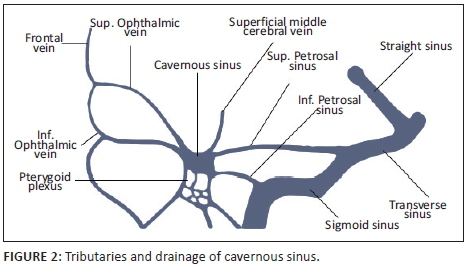

The cavernous sinuses (CS) are paired dural venous sinuses that form part of a complex network of venous channels into which the superficial venous system of the head drains. It receives venous blood from the superior and inferior ophthalmic veins, Sylvian veins and pterygoid venous plexus and in turn empties into the superior and inferior petrosal sinuses which ultimately drain via the internal jugular vein. Because of its location in the parasellar region, many neurovascular structures (including the internal carotid artery [ICA]) traverse the sinus providing an opportunity for complex interactions to occur between the structures (see Figures 1 and 2).